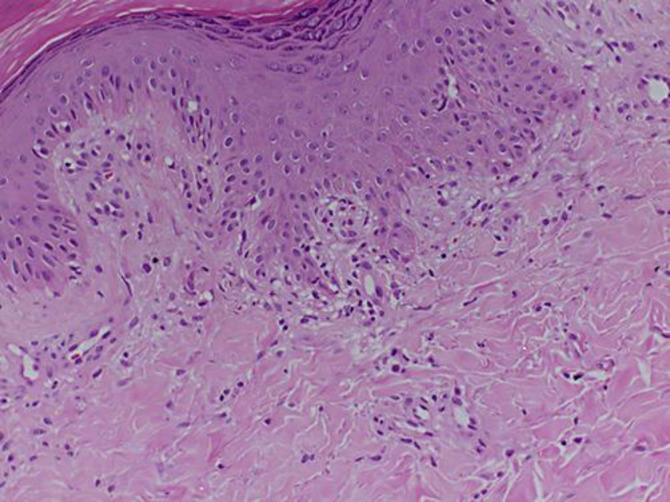

We describe an 11-year-old girl presenting with lichen simplex chronicus (LSC) and acute bilateral carpal tunnel syndrome (CTS) following herpes simplex virus type 1 (HSV-1) infection as evidenced by serological data and by detection of HSV-1 DNA in the blood with the use of PCR. Based on the literature search, this case represents the first childhood case of LSC and acute bilateral CTS following HSV-1 infection. The experience with this patient emphasizes the importance of serological tests and PCR as well as the other laboratory techniques for the accurate diagnosis and management of the disease.

我们描述了一名11岁女孩,她在感染1型单纯疱疹病毒(HSV-1)后出现慢性单纯性苔藓(LSC)和急性双侧腕管综合征(CTS),血清学数据以及通过PCR检测血液中的HSV-1 DNA证实了这一点。基于文献检索,该病例代表了HSV-1感染后LSC和急性双侧CTS的首例儿童病例。对该患者的诊治经验强调了血清学检测、PCR以及其他实验室技术对于准确诊断和管理该疾病的重要性。